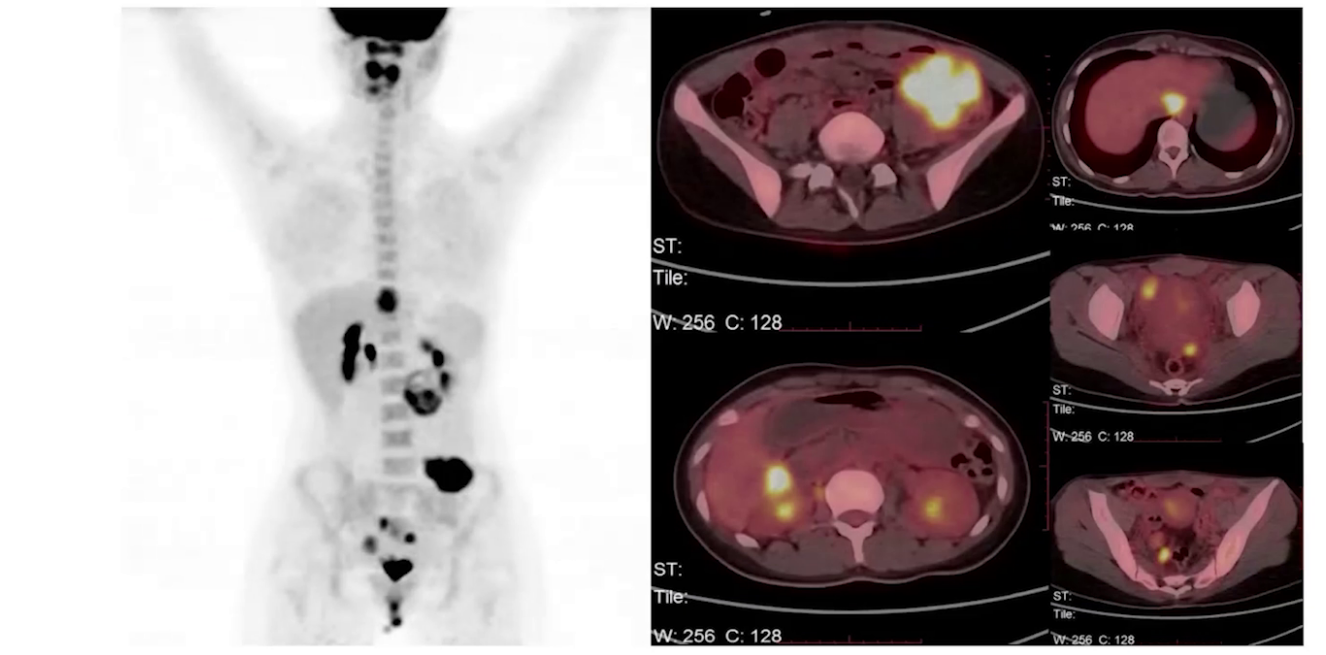

PET/CT:肝左状叶、肝右后叶旁、中腹部盆腔偏左侧、盆腔内、盆底子宫后方双侧代谢增高灶,考虑转移灶;腹盆腔积液;右肺中上叶、左肺上叶多发微小结节,未见明显代谢增高,性质待定;双侧鼻咽深部代谢增高、双侧扁桃体代谢升高,考虑炎性病变;中央骨髓代谢不均匀增高,建议随诊;颈、胸、腹部和盆腔其他部位未见明确代谢异常增高病灶。